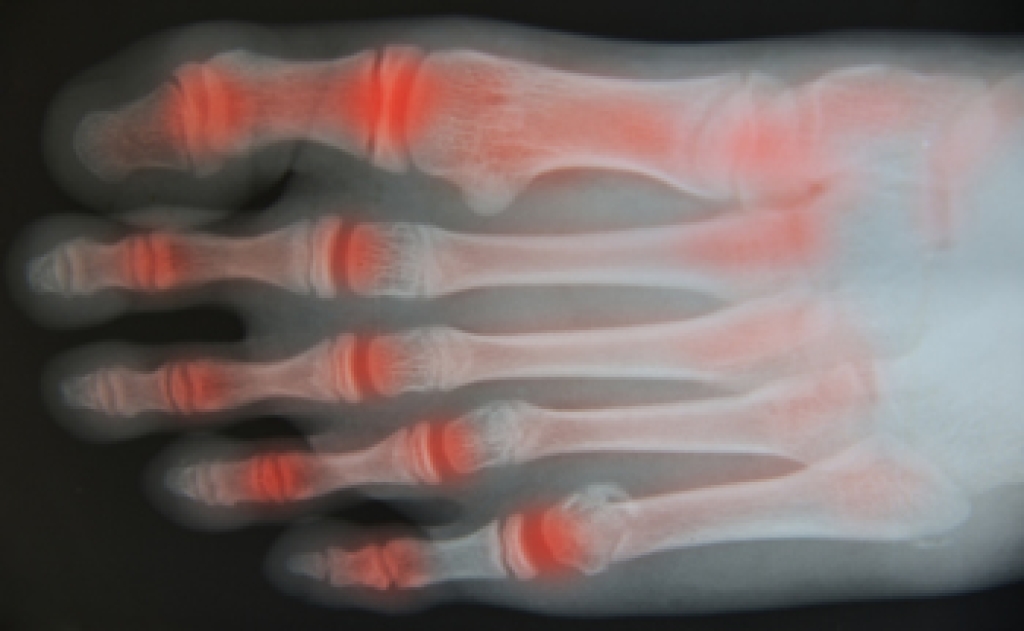

Osteoarthritis is a condition in which the protective layer of cartilage in the joints breaks down over time. This loss of cartilage causes the bones to rub together during movement, leading to pain and inflammation. Osteoarthritis is associated with aging, and often affects the small joints of the feet and ankles.

Osteoarthritis can be diagnosed through physical examination. You may also need to have an X-ray taken to assess the extent of the damage caused by arthritis.